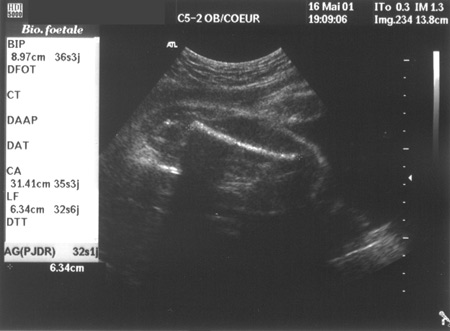

16 mai - le fémur : 63,4 mm !